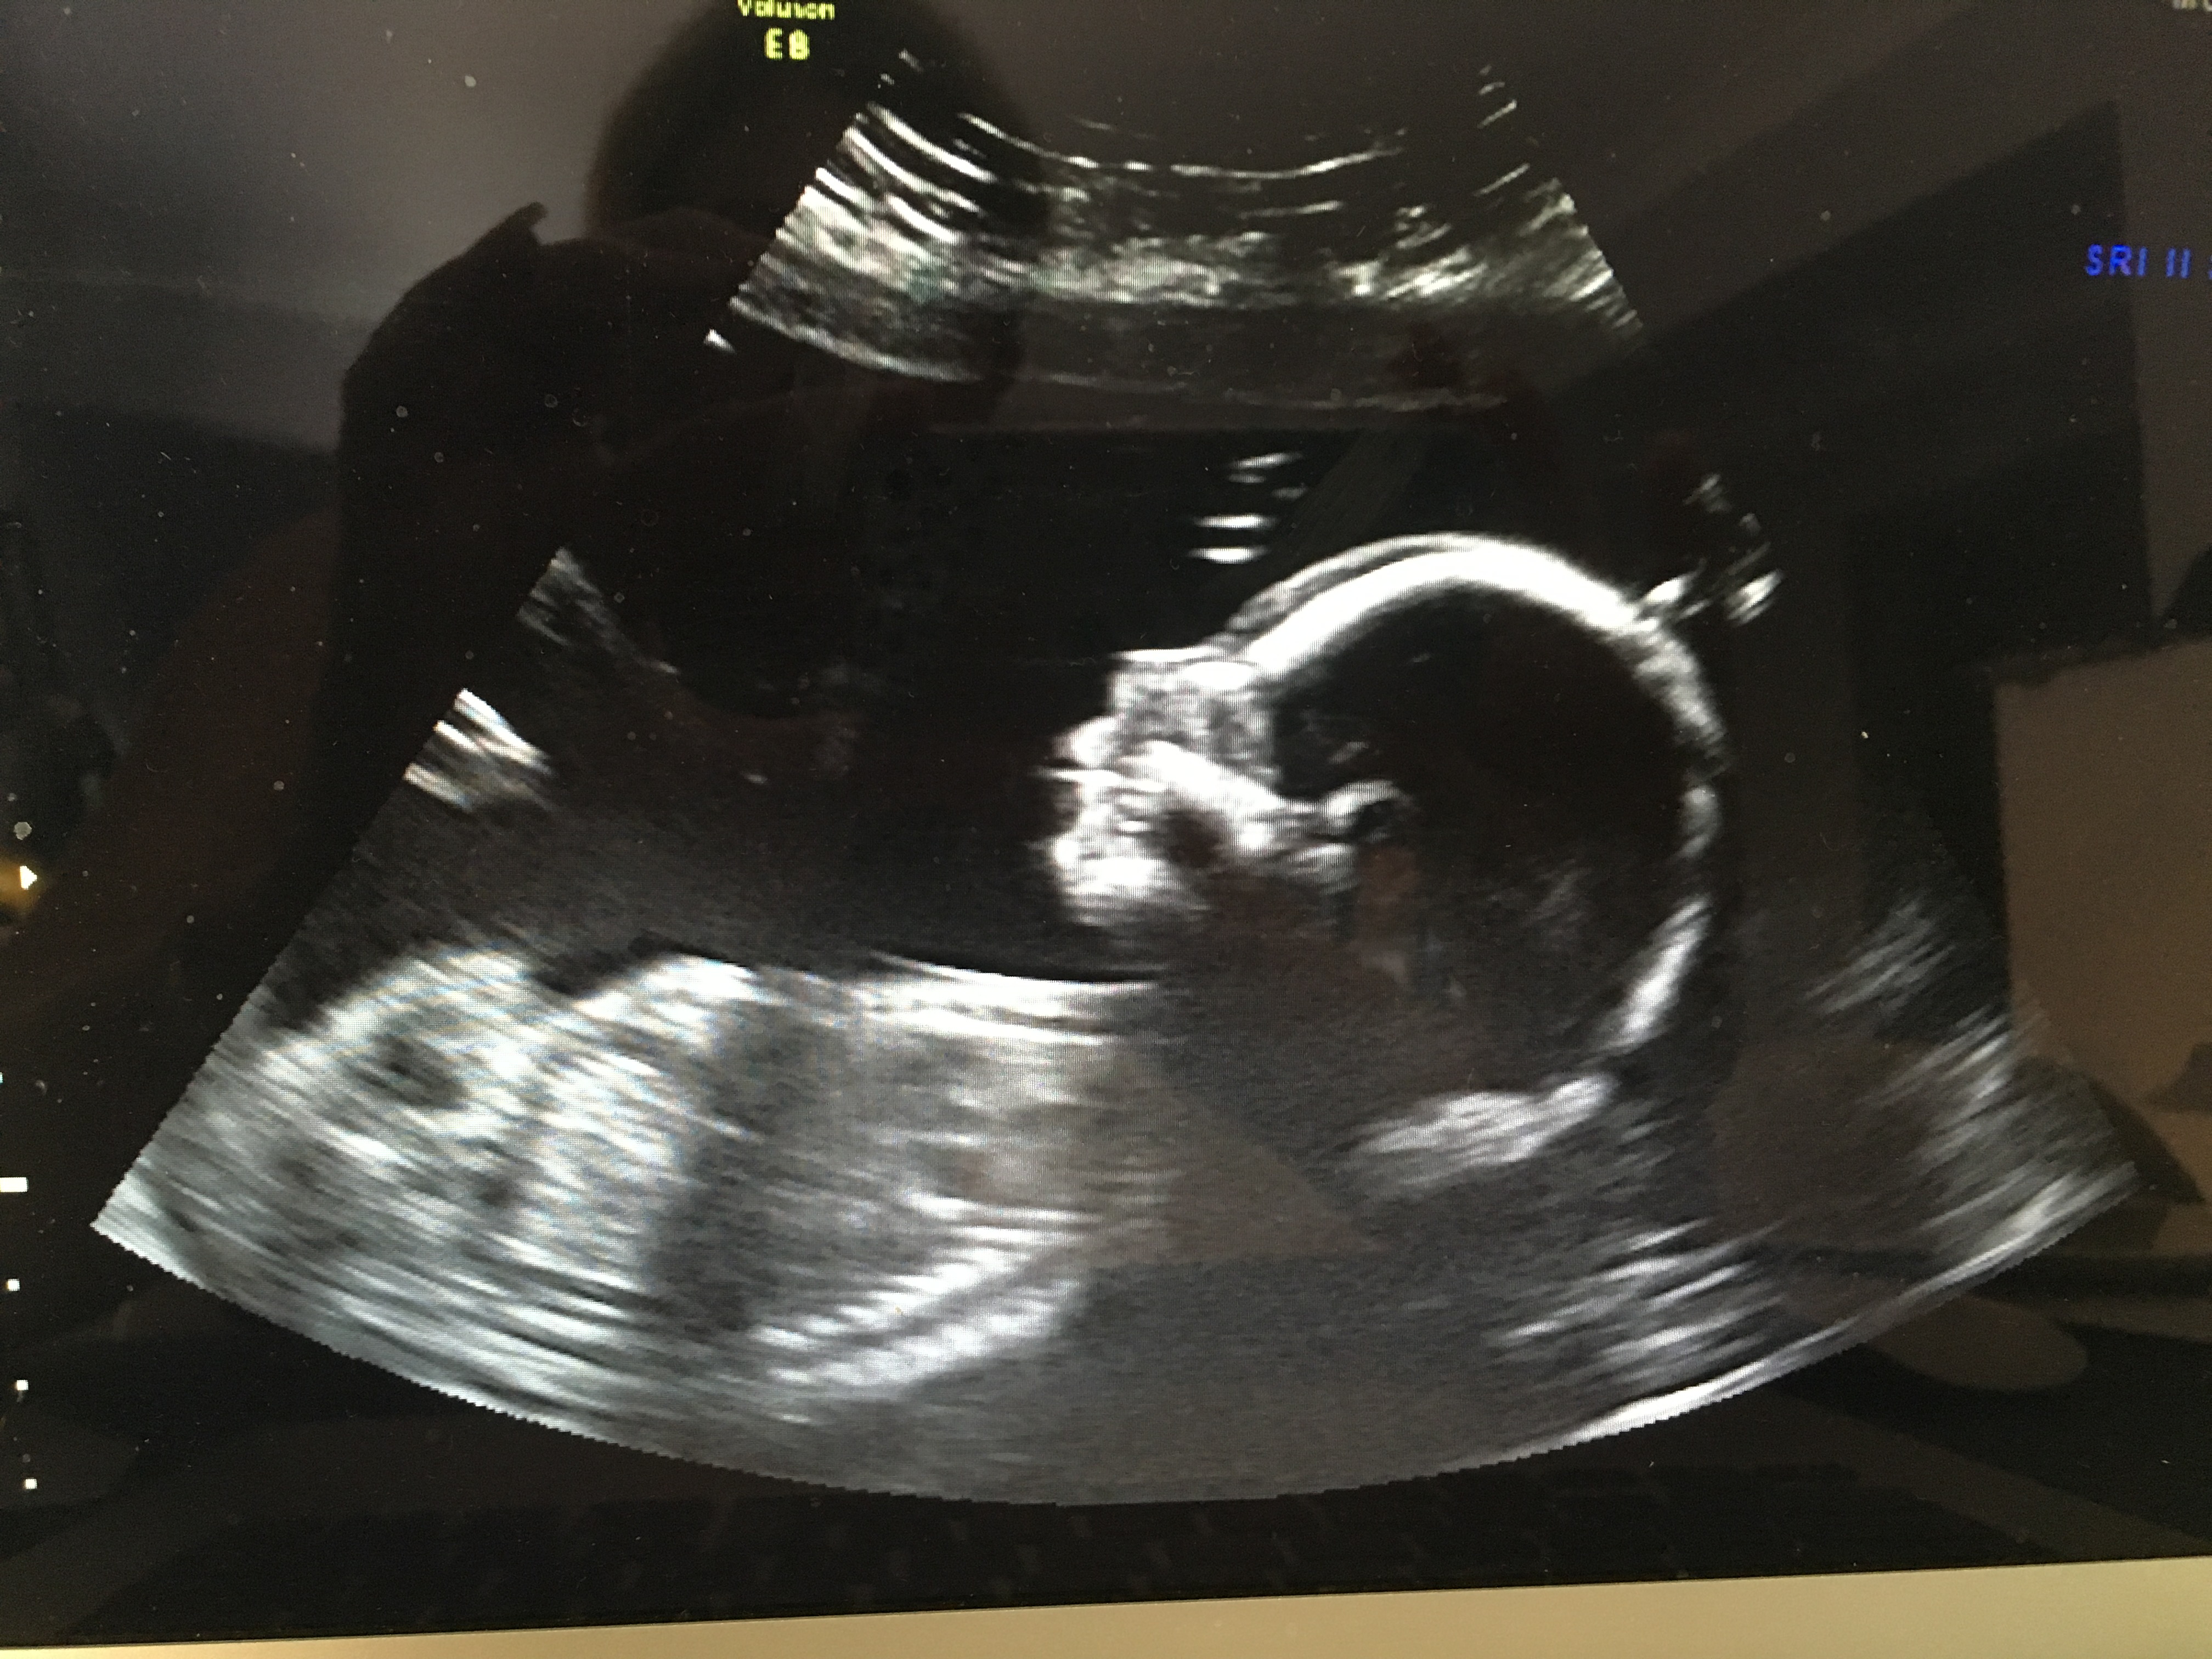

What do you think? Sonographer said confidently boy but I can see lines and think it could be swollen labia? Cord is also around baby's legs as you can see in 4d pic. Attachment 35555Attachment 35556Attachment 35557